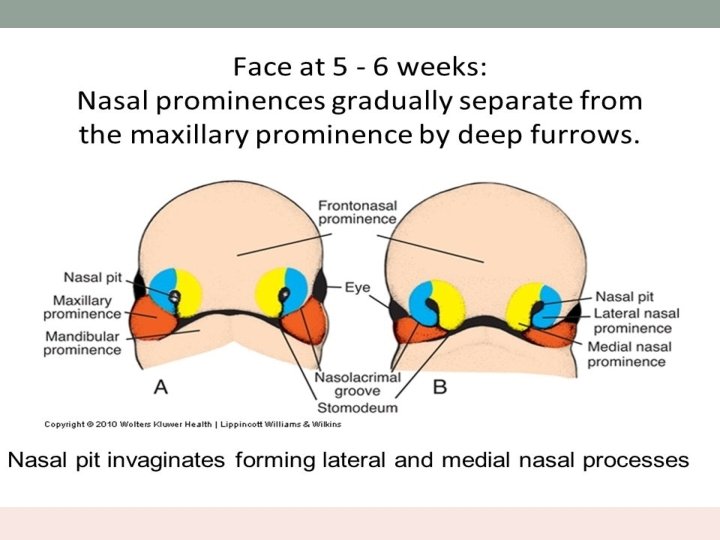

Embryology • Nasal cavity is first seen as nasal placode in the 4 th week of intrauterine life. • It is the thickening of ectoderm above the stomodeum. • Stomodeum is surrounded by superiorly – frontonasal prominence laterally – maxillary processes inferiorly – mandibular processes

• The placode thickens and sinks into the mesenchymal tissue – olfactory pit. • Lies between the proliferating medial and lateral prominences of frontonasal process. • Medial prominences fuse to form central portion of upper lip, premaxilla and primitive nasal septum. • The primitive nasal cavity and mouth are separated by bucco nasal membrane.